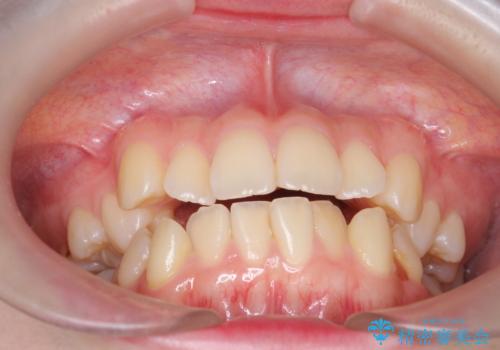

下の八重歯 歯を抜かずに インビザライン治療

- 歯並びのがたつきを主訴に来院。

抜歯してワイヤー矯正という選択肢も提案しましたが、マウスピース矯正で、歯を抜かずに並べてほしいとのことでした。

スペースを確保するために、歯をわずかに削る処置、奥歯を後ろに下げる処置(インプラント矯正)を行っています。

途中患者様のご都合で治療を中断していたため、長くかかっていますが、実質2年程度で終わる内容でした。